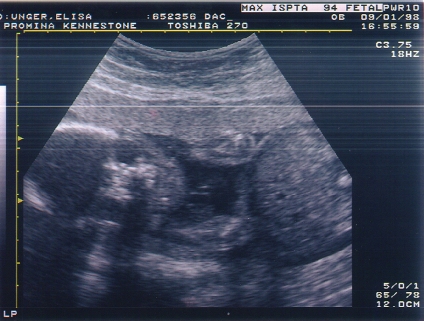

Chase @ 22 wks.jpg (108715 bytes)

Chase @ 22 wks u/s